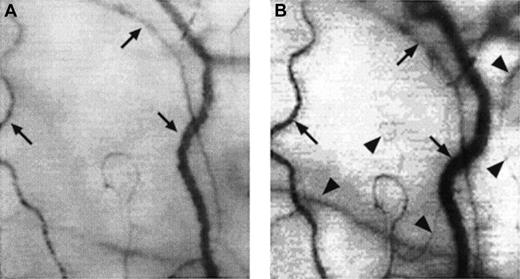

Two frame-captured images showing microvascular changes during crisis resolution in the same SCD patient.

Optical magnification, × 4.5; onscreen magnification, × 125. Focusing was aimed at the same location during crisis and crisis resolution, with the same vessel serving as its own reference baseline. (A) During crisis, there is significant reduction in vessel diameter and disappearance of capillaries and arterioles, resulting in extreme avascularity. The arrows point at the three vessels targeted for longitudinal comparison during crisis resolution. (B) An increase in vessel diameter and reappearance of capillaries and arterioles occur during crisis resolution. The vessels indicated by the arrows show a significant increase in vessel diameter. In addition, capillaries and arterioles (arrowheads) reappear during crisis resolution.

There was a significant decrease in conjunctival vascularity during painful crisis, with a close to complete absence of capillaries and a significantly reduced presence of arterioles and small venules from the steady-state conditions (Figures3 and4A). In most cases, the disappearance of capillaries and small arterioles arose as a result of the absence of blood flow into these microvessels.

A few of the sludged large vessels did not show much change in diameter during crisis; however, most of the remaining large vessels showed an averaged decrease of 36.7% ± 5.2% in the diameter (compare Figures4A and 4B).

Conjunctival red cell velocity, which was measurable in 16 of 18 SCD patients during steady-state conditions (velocity groups 1 and 2 in Table 4), either slowed significantly (46.6% ± 13.1% decrease in red cell velocity from steady-state values; P < .01) or was reduced to a trickle (≤ 0.2 mm/s or unmeasurable) when quantified within 5 hours after hospitalization for crisis treatment.

These acute microvascular abnormalities were transient, and the microvasculature reverted to steady-state values after resolution of painful crisis (postcrisis). In reality, normal steady-state values are comparable to postcrisis values made 1 month after crisis resolution. During crisis resolution, reemergence of capillaries and arterioles (reperfusion) was observed in all patients (Figure 4B).